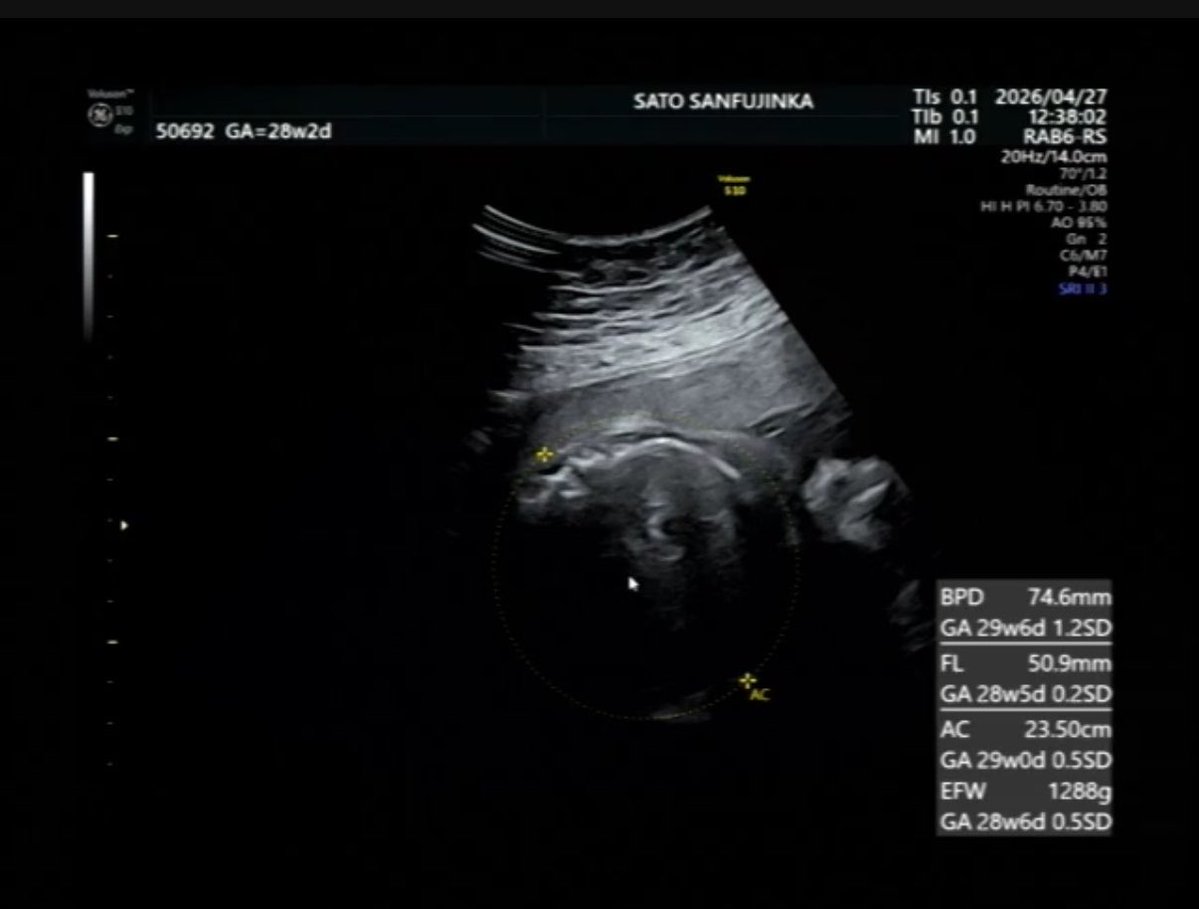

月曜日に検診も行ったんだけどお耳しか見せてくれなかった☺️ 福耳だって笑 体重は1288g 2週間で330gも増えてた👏👏 2枚目の右下に出てる数字とかってなんでGAこんなにバラバラなんだろ??どう言う意味??🥹